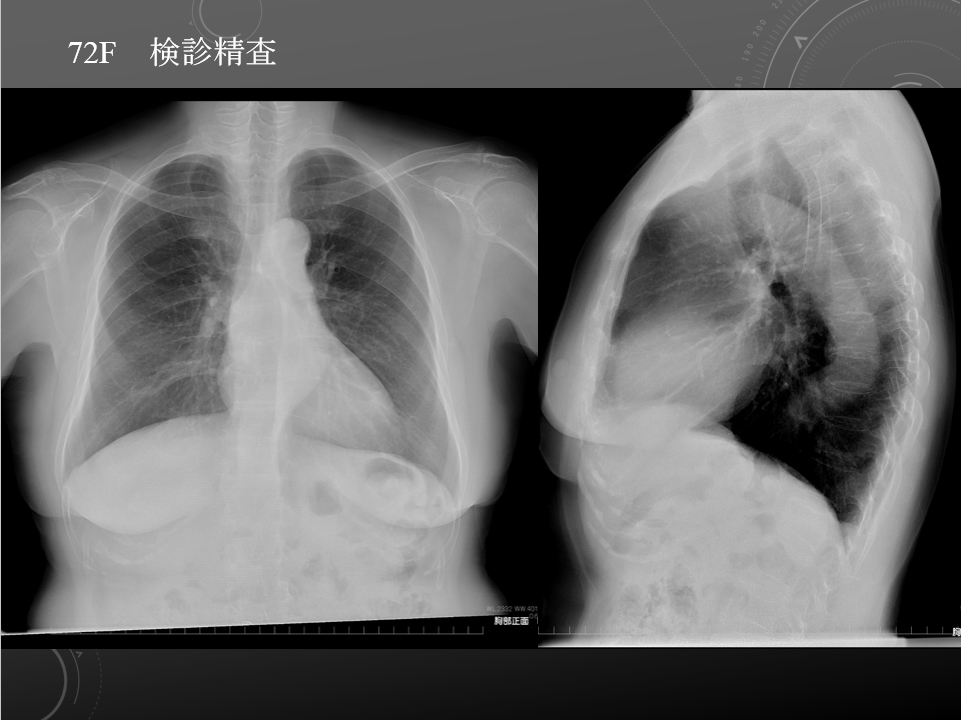

72F 健診異常 Type B2 thymoma